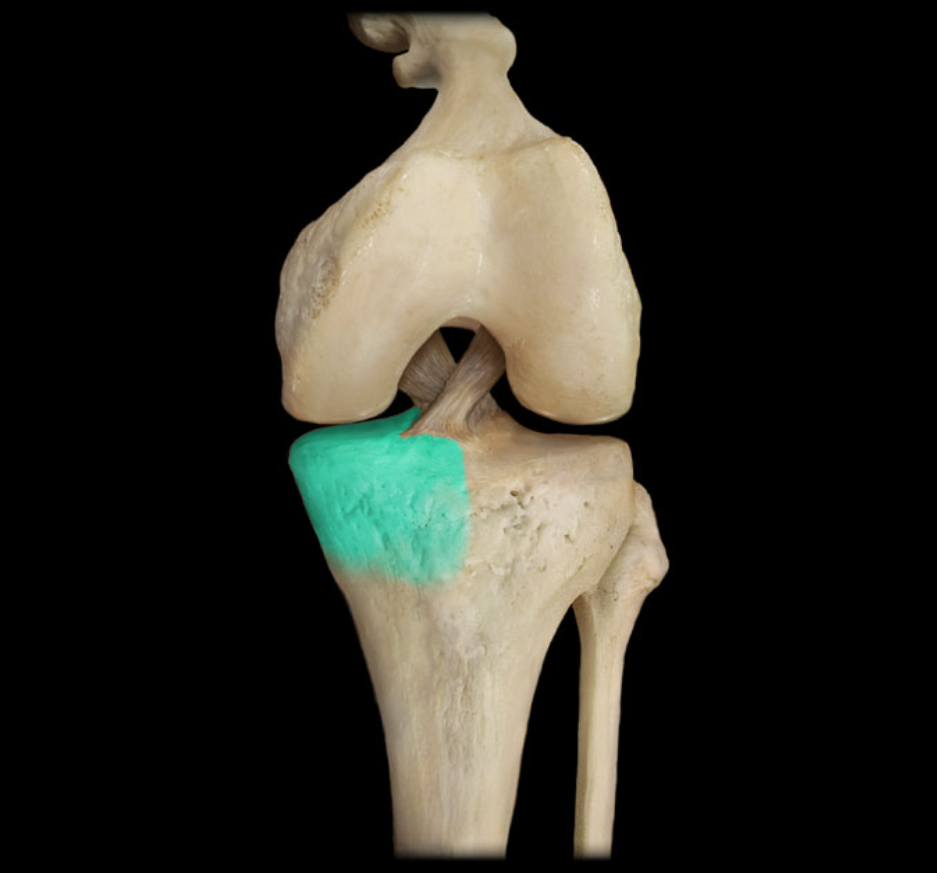

Medial condyle of tibia